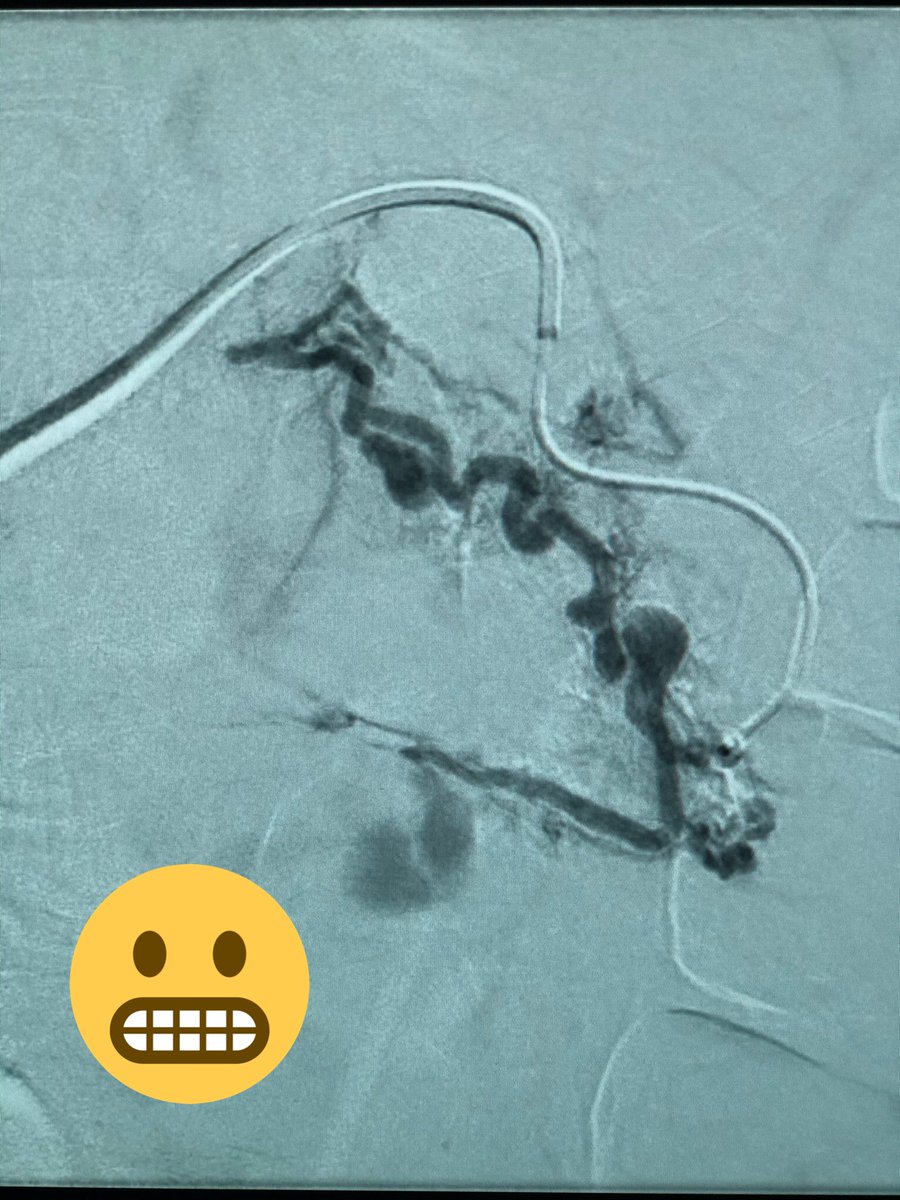

40 yo M severe L flank pain, hypotensive, admit to ICU, CT shows hemorrhage from large renal AML. Angio of torturous AML arteries, subselective run w/active🩸patient stabilized post embo, home several days later #iRad #MedTwitter #FOAMrad #PatientCare @SIR_ECS @SIRRFS @DHidlayVIR